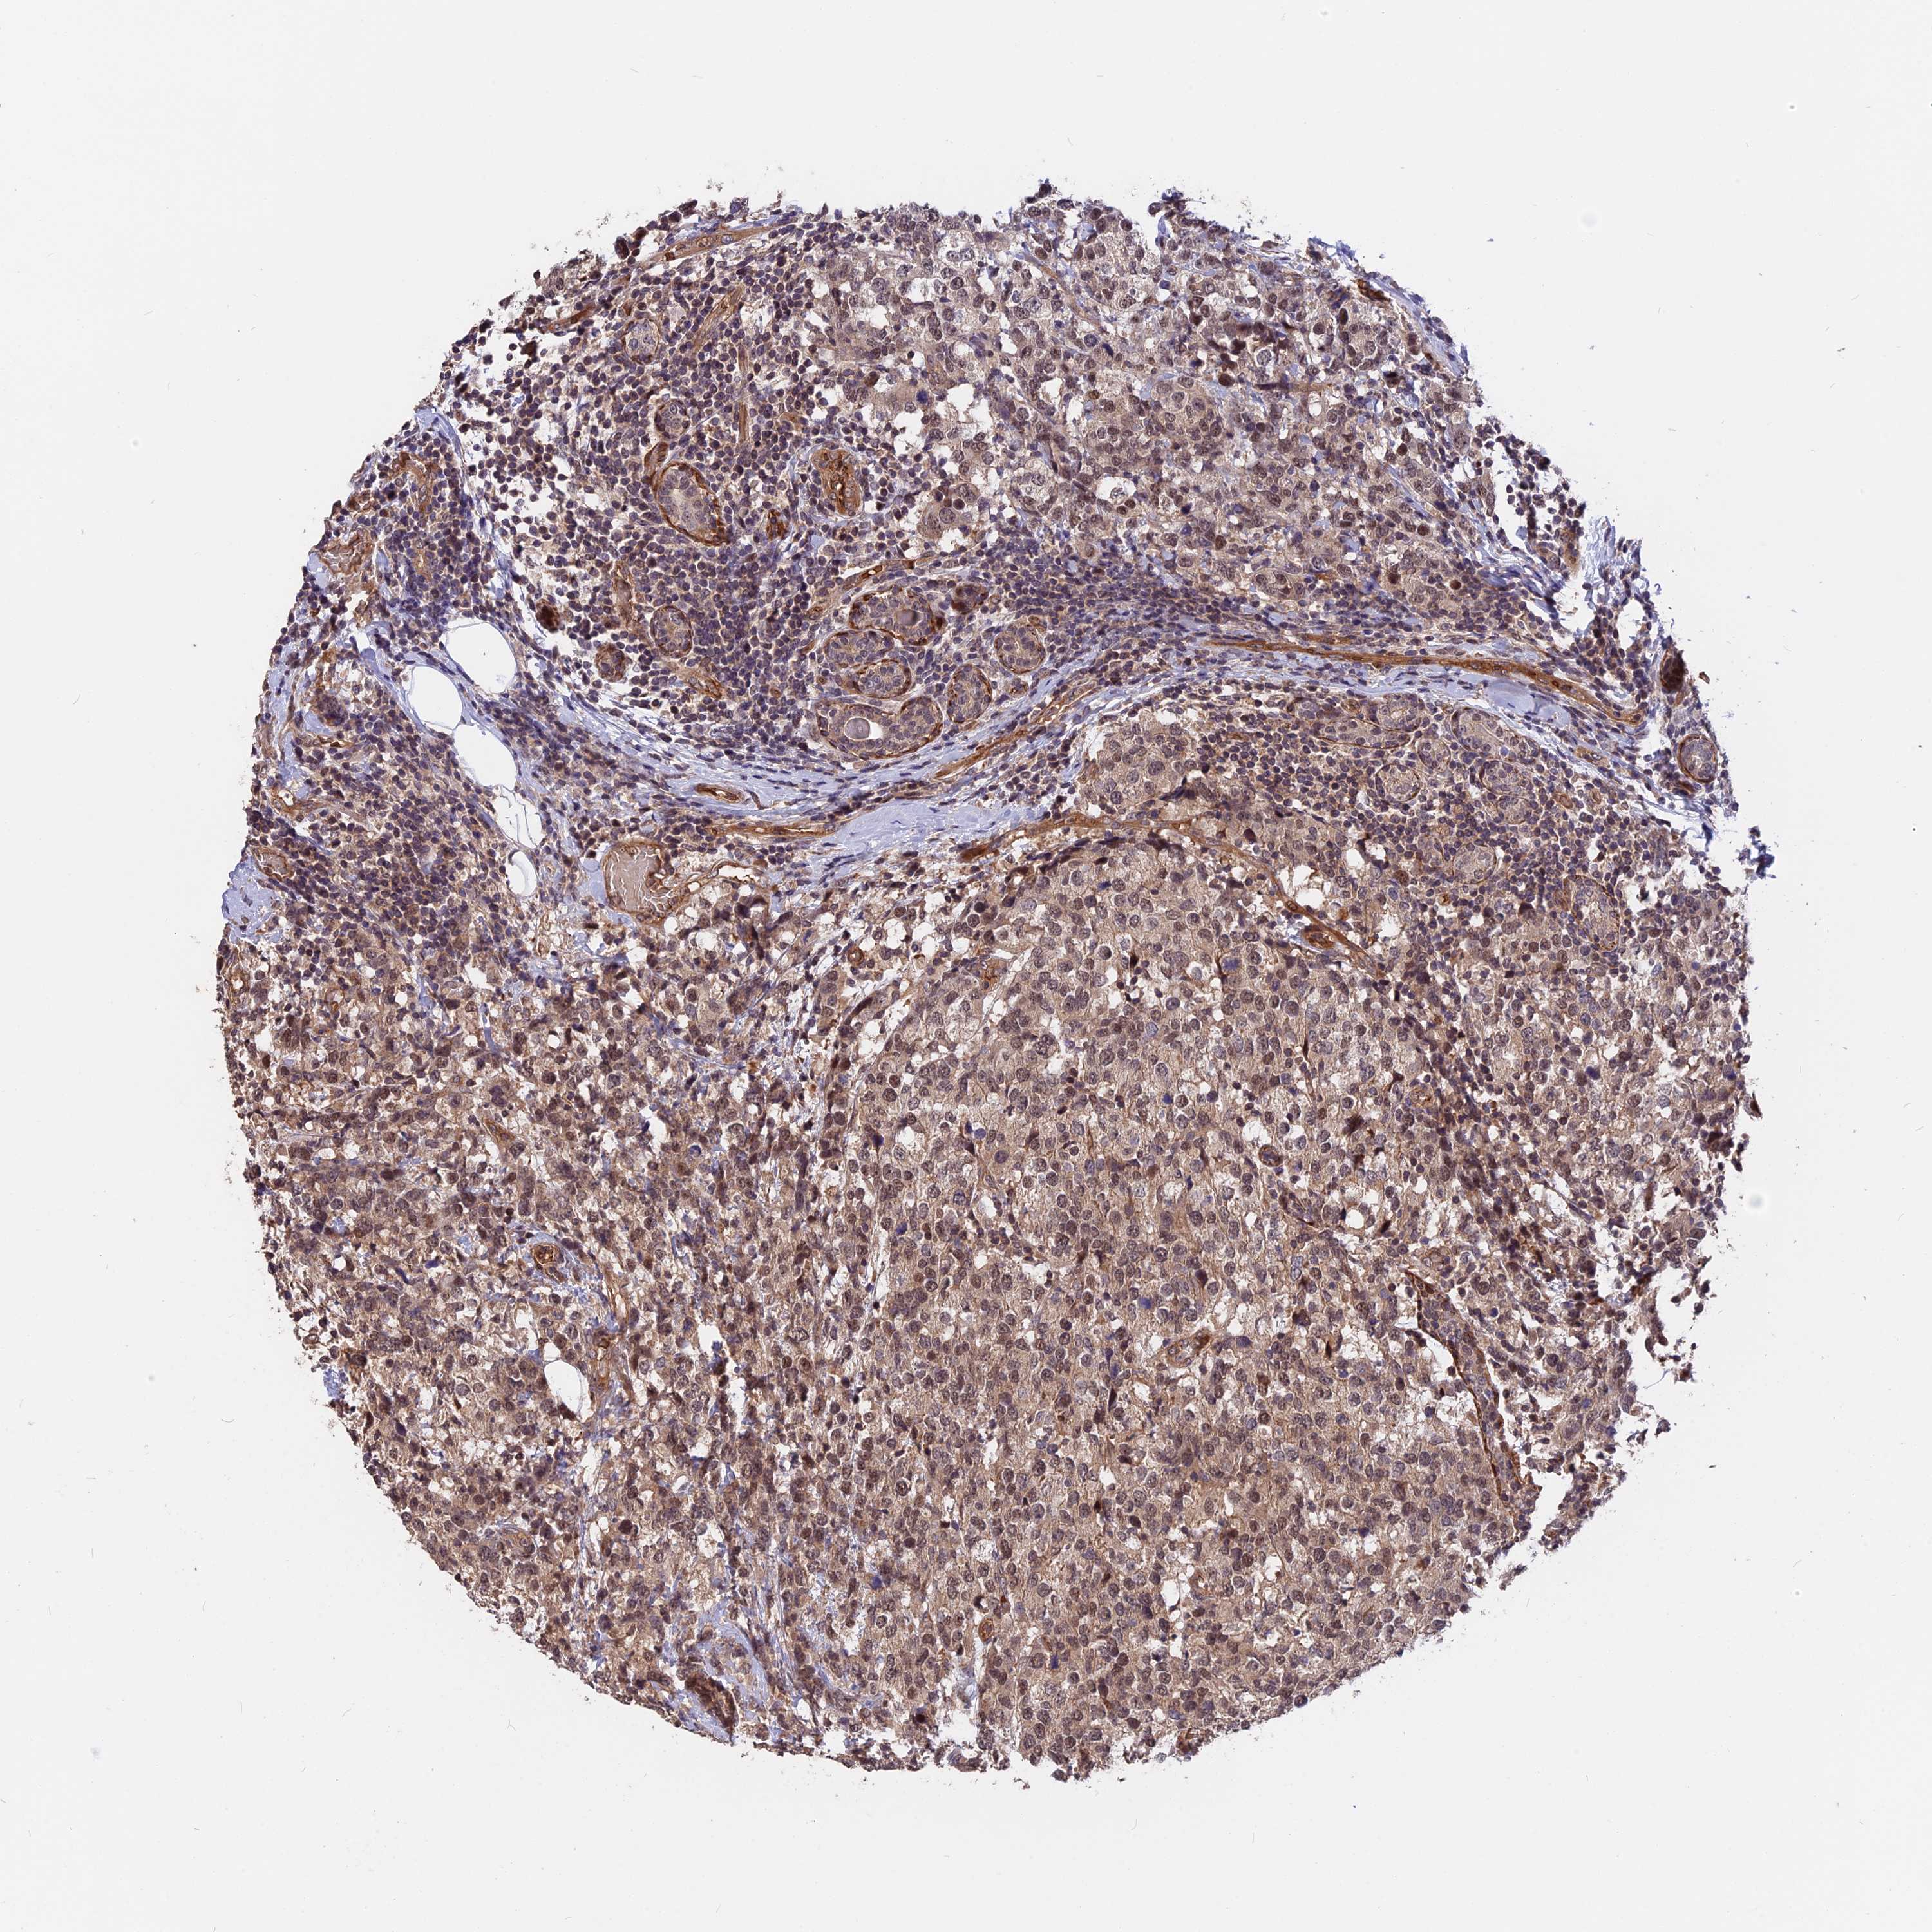

CANCER BREAST CANCER Show tissue menu

BRCA TCGA BRCA VALIDATION PROTEIN EXPRESSION

ANTIBODIES

AND

VALIDATION